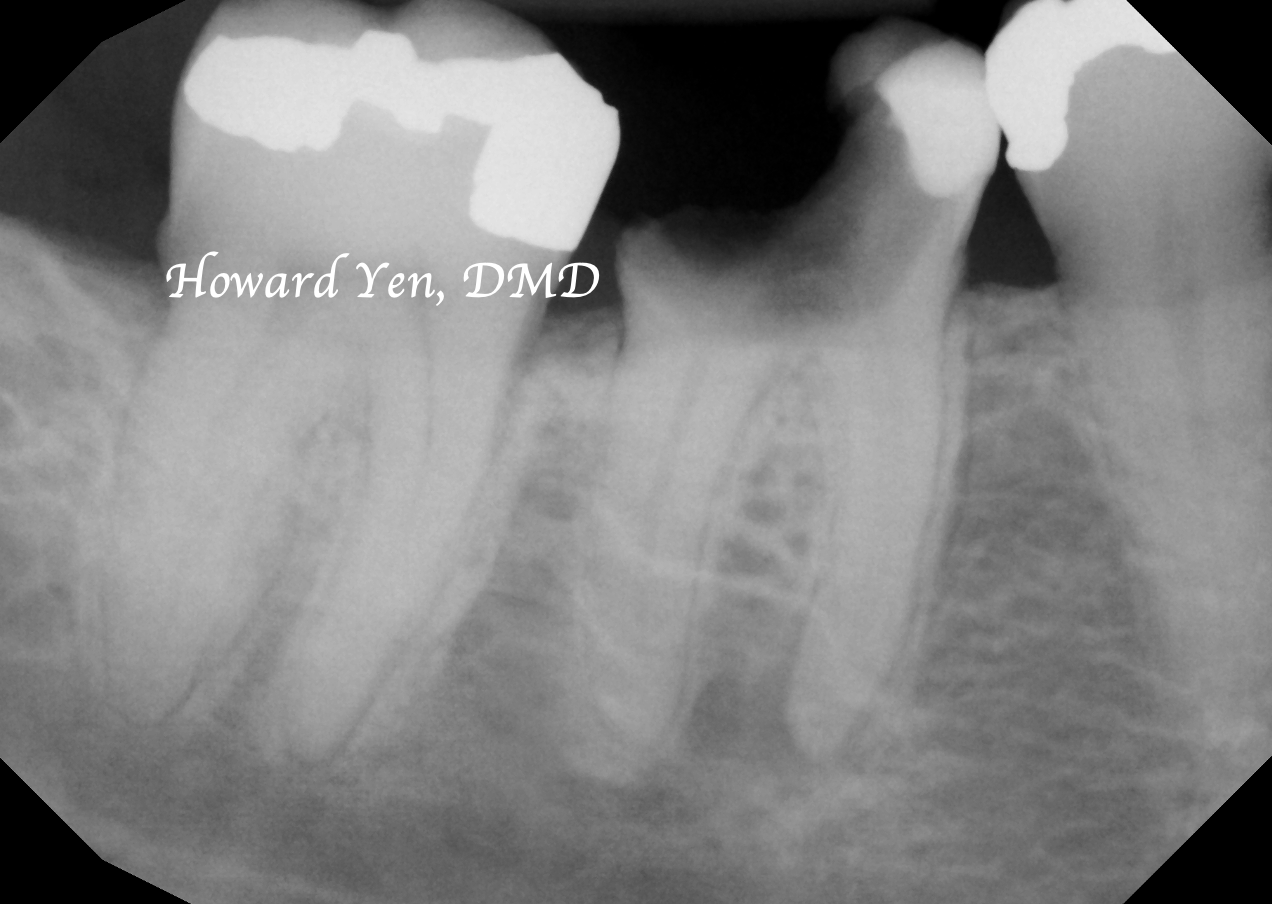

Once a natural tooth is removed from jaw bone, the jaw bone will undergo resorption (shrinkage) in volume. When there is a plan to replace the extracted tooth with dental implant, then there’s some treatment strategies to help reduce the rate of jaw bone shrinkage in order to provide adequate bone volume to receive dental implant. This procedure is often NOT necessary if there’s no plans to replace the tooth nor a strategic value (such as wisdom tooth extractions, the furthest molar in the mouth).